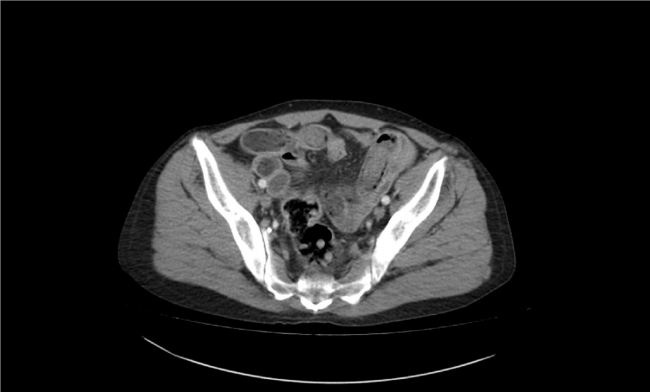

İl Emniyet Müdürlüğü Narkotik Suçlarla Mücadele Şubesi ekipleri, İran'dan Adana Havalimanı'na gelen S.R'nin (58) durumundan şüphelenerek üstünde arama yaptı. Bir suç unsuruna rastlanmayan S.R, şüpheli hareketlerinin sürmesi üzerine hastaneye götürülüp tomografi cihazıyla kontrol edildi.

İran uyruklu S.R'nin midesinde tespit edilen 49 paketteki 775 gram saf eroin endoskopiyle alındı.